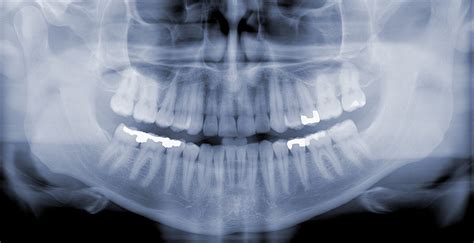

Registrácia nového pacienta začína dôkladnou vstupnou prehliadkou. Počas nej lekár zhodnotí celkový stav vašej ústnej dutiny, zhotoví digitálne RTG snímky a vypracuje individuálny liečebný plán. Tento proces umožňuje spoznať vašu anamnézu a navrhnúť postupy, ktoré najlepšie vyhovujú vašim potrebám aj rozpočtu.